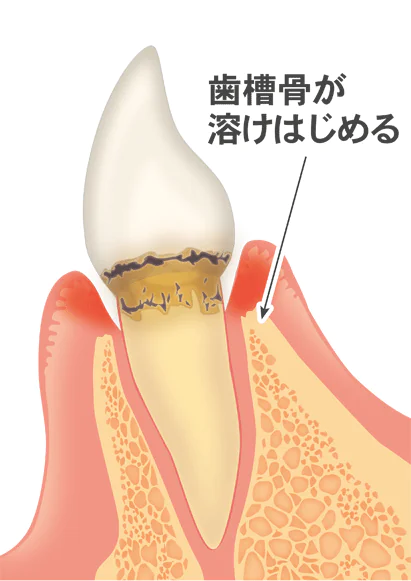

軽度歯周病

軽度歯周病では、歯槽骨が歯根の長さの3分の1まで消失しています。歯ぐきの炎症が進行し、歯周ポケットができ、歯槽骨が溶け始めます。